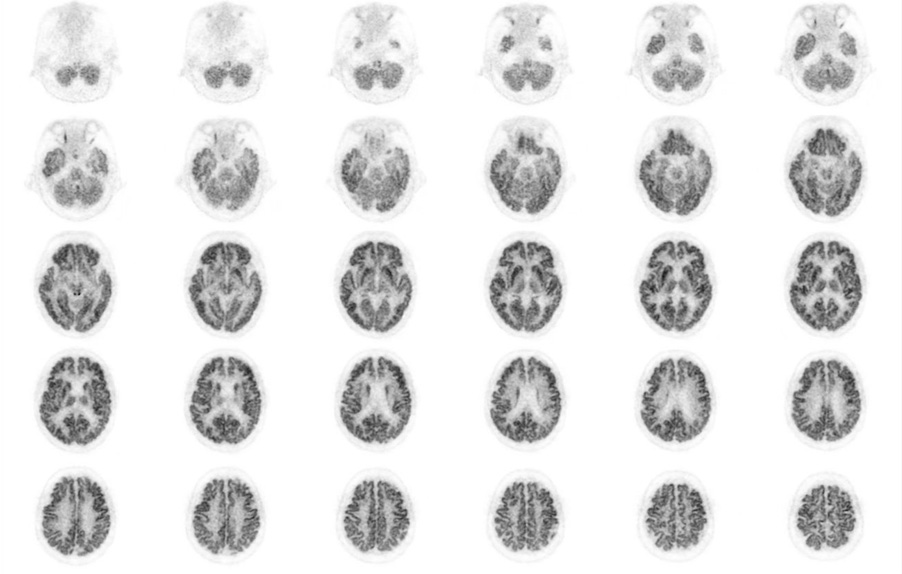

Head / Case1 : FDG

Axial

- Imaging protocol

- Injected dose: 2.87 MBq/kg, 18F-FDG

- Uptake time: 42 minutes

- Scan time: 30 minutes